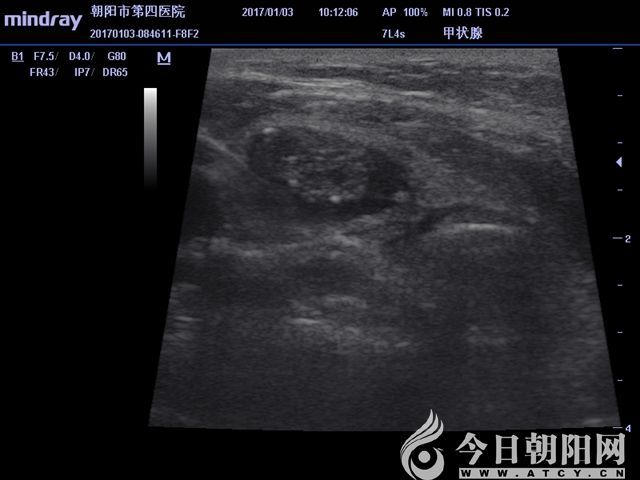

超聲顯示囊實結合性病變

患者為65歲女性,發(fā)現(xiàn)左右側頸部包塊1個月,通過超聲檢查考慮甲狀腺腺瘤伴出血。患者從心理上不能接受頸部手術后切口瘢痕,拒絕手術切除,要求微創(chuàng)治療。針對患者要求,該院外科團隊為其設計了治療方案——行甲狀腺微波消融術。手術采用局麻,在超聲影像引導下,順利準確穿刺,抽出積血后,再于實性病變處用活檢針穿刺取病理,證實良性病變。